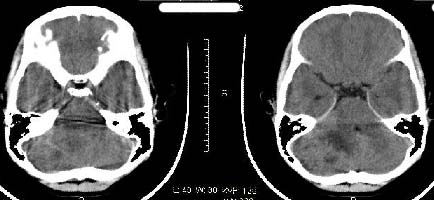

以下是引用子期在2009-6-10 21:34:00的发言:[br]髓母细胞瘤一般位于中线附近和小脑蚓部,该病灶位于右侧小脑半球,倾向于毛细胞型星形细胞瘤,当然也不能完全排除髓母细胞瘤。

以下是引用随光逐影在2009-6-10 22:26:00的发言:[br]考虑右侧小脑胶质瘤,髓母细胞瘤待排。

以下是引用影象小泰斗在2009-6-10 22:14:00的发言:[br]年龄及影像表现军符合小脑星形细胞瘤表现![br]期待病理结果!